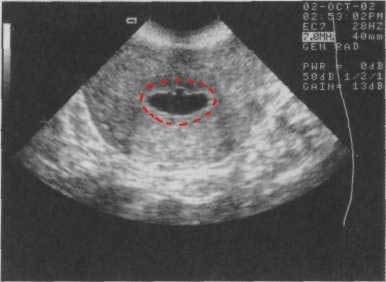

Для диагностики ветеринары рекомендуют проводить рентгенографию и анализы, чтобы подтвердить наличие инфекции. Лечение обычно включает антибиотики, поддерживающую терапию и корректировку условий содержания, таких как температура и влажность. Специалисты акцентируют внимание на важности своевременного обращения к ветеринару, так как запущенные случаи могут привести к серьезным осложнениям. Правильный уход и профилактика помогут избежать развития пневмонии у черепах.

Для более точной диагностики могут потребоваться дополнительные исследования. Ветеринар может назначить рентгенографию, чтобы визуализировать легкие и выявить возможные воспалительные изменения. Также может быть проведен анализ крови для оценки общего состояния здоровья черепахи и выявления признаков инфекции.